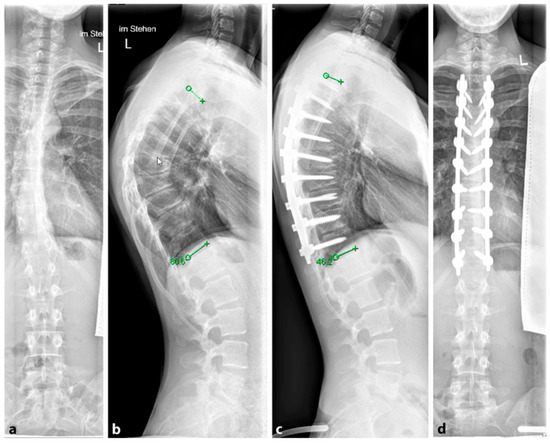

Several surgical techniques have been proposed to address SD, all of which involve three key steps: release of spinal structures, correction of the kyphosis (aiming for at least 50% correction), and spondylodesis with instrumentation [96]; see Figure 11. Some techniques include an anterior release to facilitate posterior curve correction, but the potential benefits of this approach remain uncertain, and it may lead to a higher occurrence of unfavorable effects such as higher complications rates, blood loss and operation time [98,99,100]. Earlier studies have shown favorable outcomes in terms of pain relief and spinal deformity correction following surgical intervention for SD with the most common complications reported being neurological (such as paraplegia), infectious, and respiratory in nature [93,95]. For rigid curvatures, anterior release followed by dorsal instrumentation and spondylodesis was the method of choice until about 20 years ago. However, in several studies, dorsal instrumentation with osteotomies and shortening of the dorsal column achieved comparable results to anterior–posterior procedures [101,102]. Lee et al. evaluated 17 studies and a total of 1147 patients in a meta-analysis. Here, the correction of the kyphotic malalignment between dorsal instrumentation with osteotomies and anterior–posterior spondylodesis was comparable [103]. Despite this, anterior release, fusion and posterior spinal fusion experienced significantly more complications than the posterior spinal fusion alone [101]. Therefore, it is not recommended to subject the patient to additional surgery (i.e., anterior release and fusion). A single posterior approach is adequate to achieve sagittal correction with a balanced spine and fewer associated complications.

4.4.1. Selection of the Instrumentation Range

The determination of the instrumentation range is certainly dependent on the chosen surgical procedure. The upper instrumented vertebra (UIV) is usually the proximal vertebra that still belongs to the curvature [104]. The selection of the lowest instrumented vertebra (LIV) can be the first lordotic vertebra (FLV) or the sagittal stable vertebra (SSV) according to Cho et al. [105]; see Figure 12. However, in the meta-analysis by Gong et al., instrumentation of the SSV proved to be superior to the FLV [106]. In this meta-analysis, the incidence of distal junctional kyphosis (DJK) in SD was reported to be 20.8%, and of these cases, 27.8% of patients had to be revised; 5.9% of the SSV cohort and 43.6% of the FLV cohort developed DJK [106].